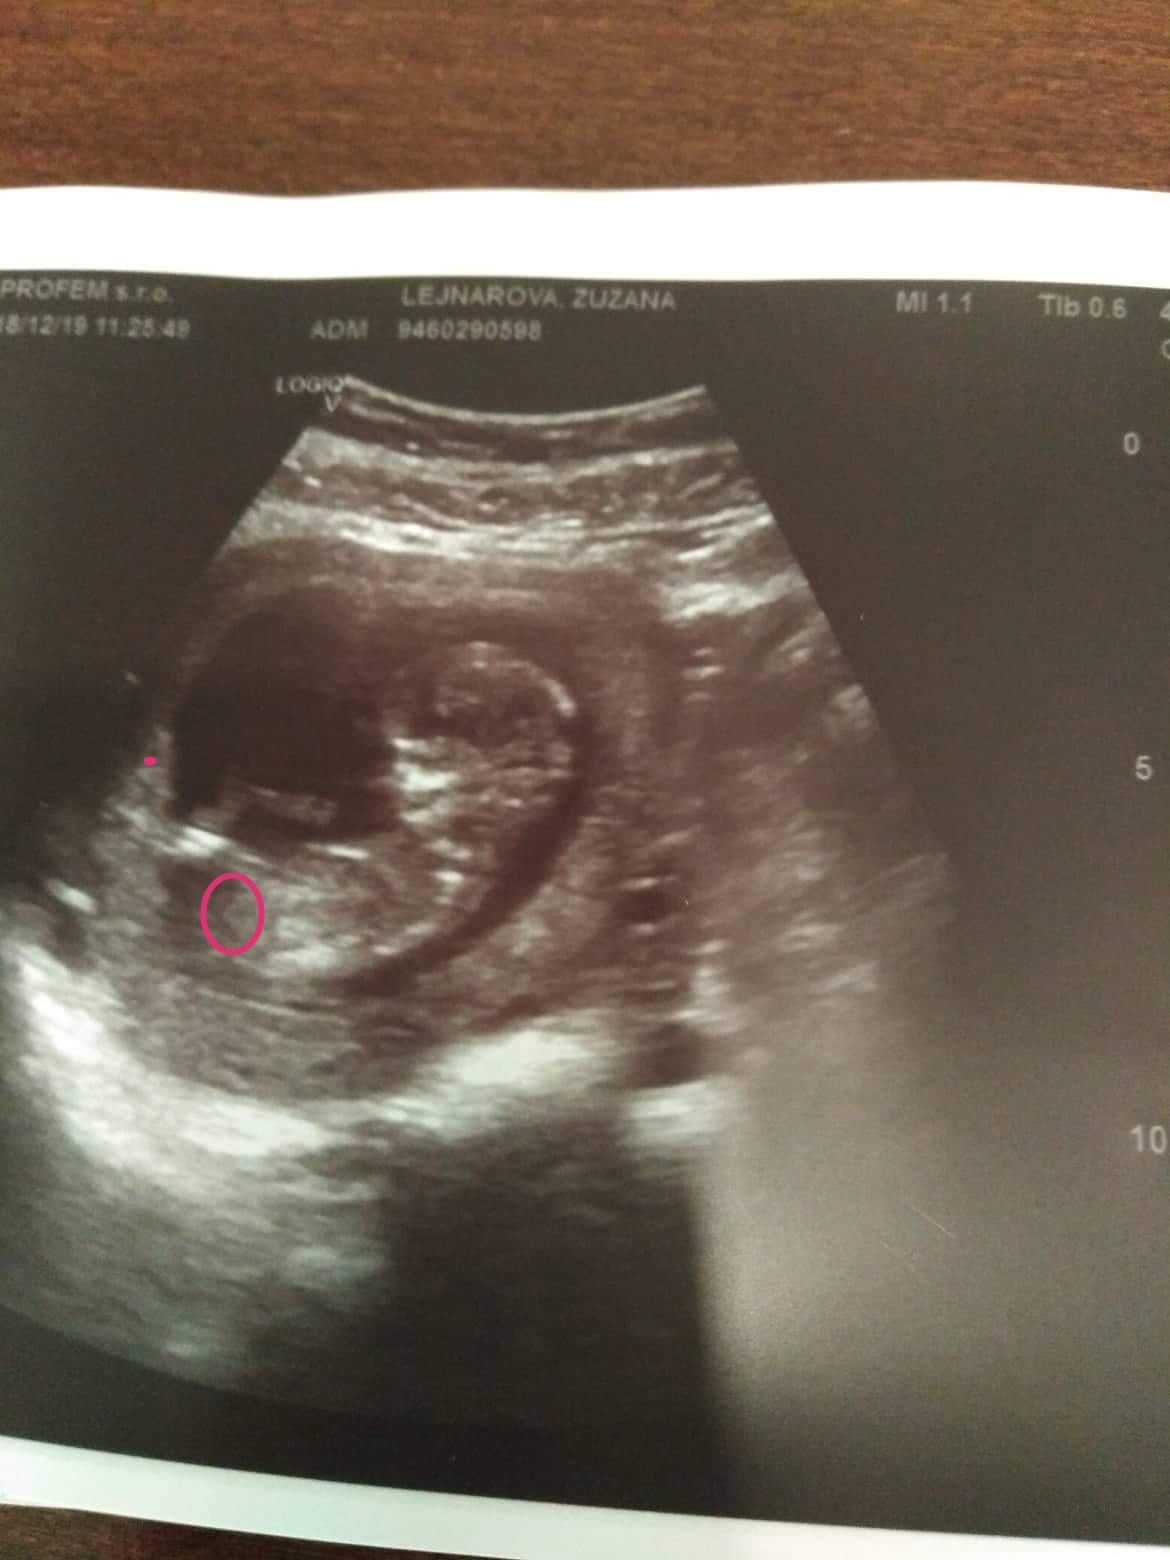

Holka nebo kluk. Vidíte tam něco?

@krupka3 Tady je náš 14tt a dr přímo řešila hrbolek. Je vidět i na fotce 🙂 a myslím že ten 15tt nebude ještě jinak.

Tam podle mě vidět nic není.. Blbá fotka na určování pohlaví 🙂